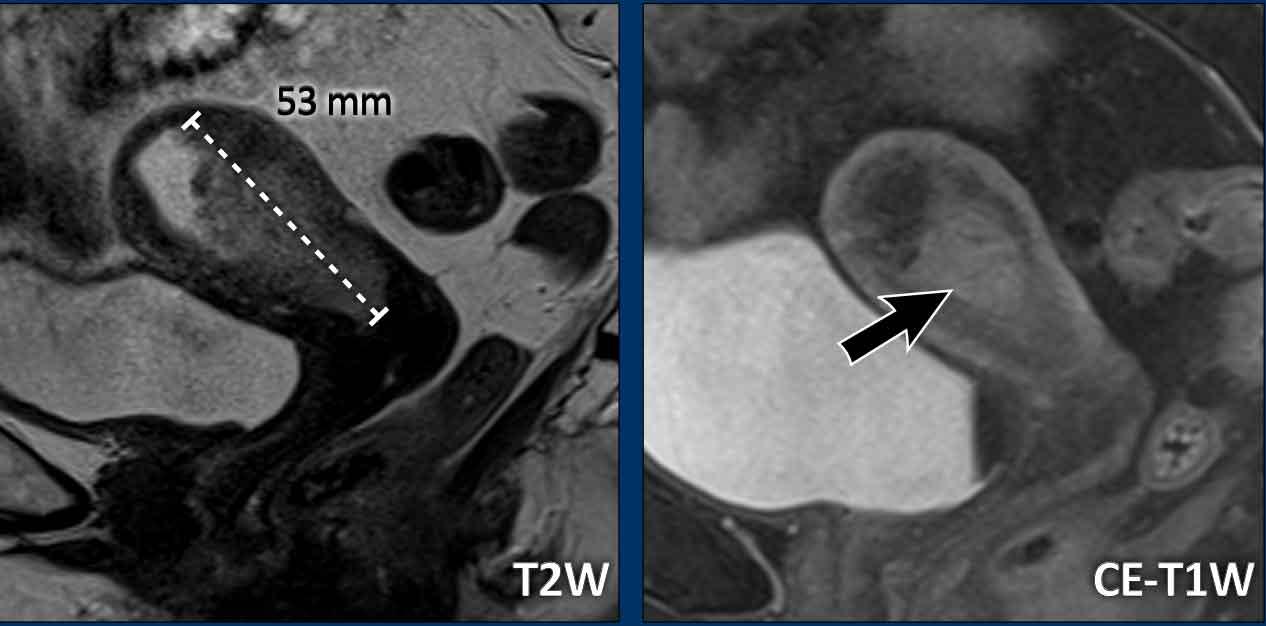

Kích thước khối u

Tùy thuộc vào độ tuổi của bệnh nhân, các khối u nội mạc tử cung có thể biểu hiện tăng tín hiệu nhẹ (xem hình) hoặc giảm tín hiệu (ở bệnh nhân trẻ tuổi hơn) so với cơ tử cung bình thường.

Các khối u thường được nhận diện rõ ràng trên chuỗi xung T2W.

Hình thái của khối u có thể biến đổi từ một khối có ranh giới rõ đến dạng dày lan tỏa của lớp nội mạc tử cung.

Hình ảnh

Ví dụ về một khối u nội mạc tử cung dạng tạo khối, thường dễ đo nhất. Điều quan trọng là phải đo đường kính dài nhất của khối u.

Trong trường hợp này, đường kính dài nhất của khối u được quan sát rõ nhất trên mặt phẳng đứng dọc (sagittal).

Trong các trường hợp dày lan tỏa hơn dọc theo lớp nội mạc tử cung, việc đo kích thước khối u có thể khó khăn hơn.

Hãy kiểm tra khối u trên nhiều mặt phẳng và tìm kích thước dài nhất có thể.

Trong trường hợp này, đường kính dài nhất của khối u được quan sát rõ nhất trên mặt phẳng ngang (axial) (hình).

Kích thước toàn bộ tử cung

Kích thước toàn bộ tử cung là thông tin quan trọng cần báo cáo vì nó ảnh hưởng đến chiến lược phẫu thuật, bao gồm lựa chọn đường vào qua âm đạo, nội soi ổ bụng hay mổ mở qua thành bụng.

Nếu kích thước tử cung quá lớn (ví dụ: >10 cm), đây sẽ là chống chỉ định để thực hiện phẫu thuật qua âm đạo hoặc nội soi ổ bụng.

Kích thước tử cung thường được đo trên mặt phẳng đứng dọc (sagittal) theo 2 chiều: đầu-đuôi (bao gồm cổ tử cung) x trước-sau (hình).